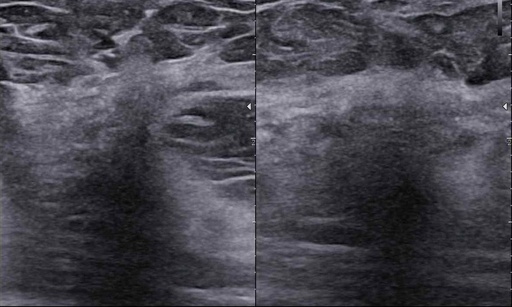

Ultrasonografia jest jedną z czterech głównych metod w diagnostyce chorób piersi. Obecna sytuacja epidemiologiczna, czyli ciągły wzrost zachorowań na raka piersi u kobiet, wymaga od nas dyskusji na ten temat. Od 20 lat zajmuję się problematyką diagnostyki gruczołu piersiowego. Dużo słucham, szkolę się, jak również przekazuję swoją wiedzę Państwu na licznych kursach, warsztatach, kongresach i sympozjach.

Zapraszam Państwa – wszystkich miłośników kobiecej piersi – do udziału w cyklu webinarów dotyczących głównie diagnostyki i leczenia chorób piersi. Będę się koncentrował na przekazywaniu Państwu praktycznej wiedzy oraz na tym, jak ją wykorzystać w ultrasonograficznej diagnostyce piersi.

Nagranie webinaru: BI-RADS-usg case story

Czy my rzeczywiście potrafimy czytać tę skalę? Dlaczego tyle jest rozbieżności?

Czy podział BIRADS 4 ma sens? Jak radzić sobie  z BIRADS 4a, b, c? Morfologiczne wskazówki